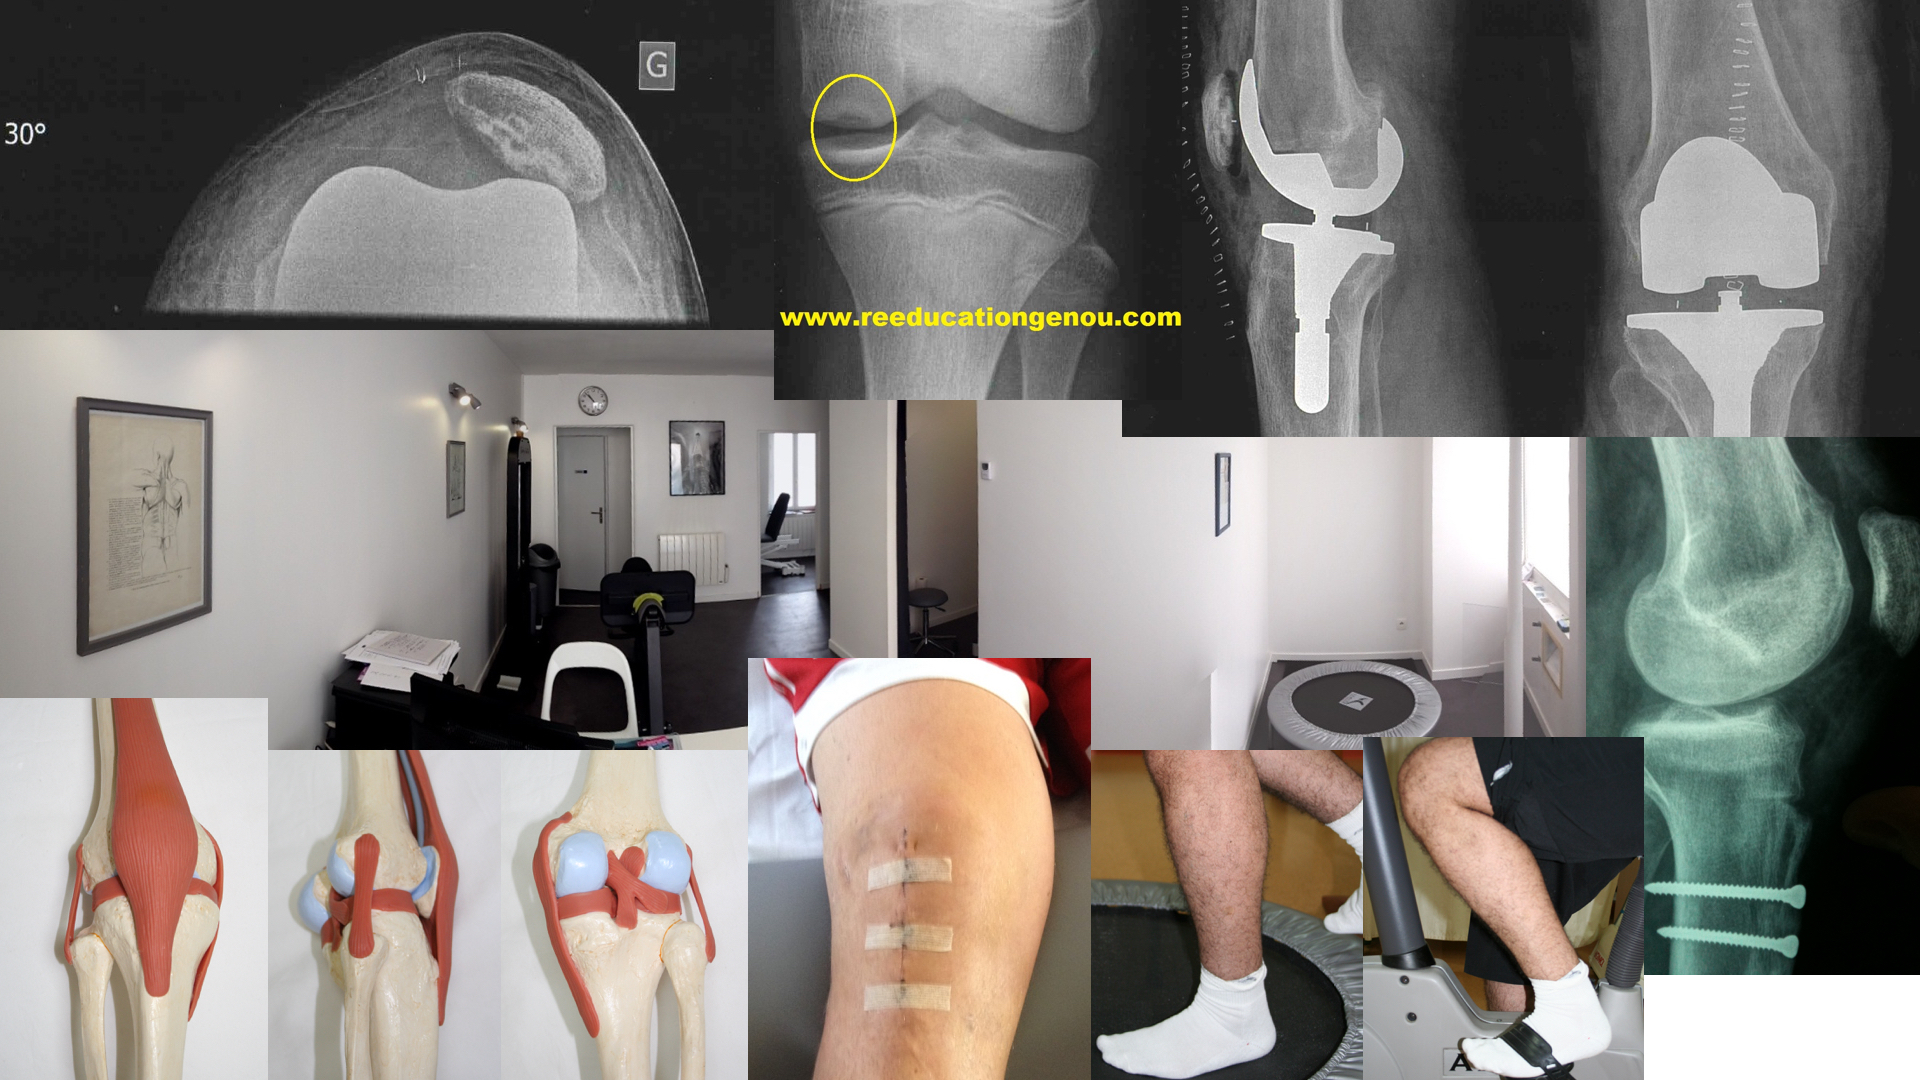

reste d'hématome le long du prélèvement des tendons ischios jambiers